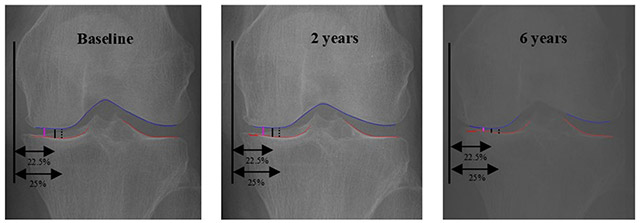

무릎 골관절염의 중증도 평가는 일반적으로 X-ray에서 대퇴골과 경골 사이의 관절 간격(joint space width, JSW)을 측정해 이뤄진다. 그러나 기존 방식은 관절의 특정 위치(JSW225, JSW250 등)를 기준으로 간격을 측정하기 때문에 환자마다 다른 연골 마모 위치나 비대칭적인 관절 손상을 충분히 반영하지 못할 수 있다는 한계가 지적됐다.

연구팀이 제안한 oJSW는 AI가 X-ray 영상에서 관절 구조를 분석해 가장 좁아진 지점을 자동으로 탐색하고, 해당 위치에서 관절 간격을 수직으로 측정하는 방식이다. 고정된 위치가 아닌 실제 마모가 가장 심한 부위를 기준으로 간격을 계산함으로써 개인별 관절 손상 상태를 더욱 정확하게 반영하는 것을 목표로 한다.

• 무릎 X-ray에서 관절 간격 측정 방식 비교. oJSW(보라색)는 AI가 관절에서 가장 좁은 지점을 찾아 측정하는 방식으로, 기존 고정 위치 측정(JSW22.5·JSW25)과 차이가 있다. (초기·2년·6년 시점 비교) /이미지=서울대병원

▲ 무릎 X-ray에서 관절 간격 측정 방식 비교. oJSW(보라색)는 AI가 관절에서 가장 좁은 지점을 찾아 측정하는 방식으로, 기존 고정 위치 측정(JSW22.5·JSW25)과 차이가 있다. (초기·2년·6년 시점 비교) /이미지=서울대병원